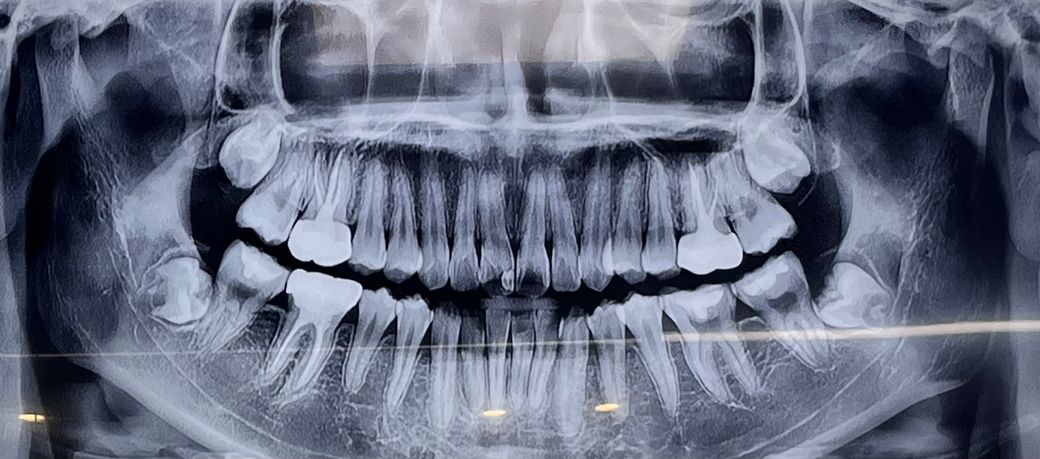

x-ray 사진으로 보았을 때는 인접면 충치 뿐만 아니라 교합면에도 어느정도 충치 및 손상이 있을 것으로 보입니다. 광범위한 수복이 있을 경우에는 레진으로 하는 것이 오히려 치아에 안 좋은 영향을 줄 수 있으므로 인레이 이상의 치료를 권하고 있습니다.

환자분 치아는 교합면에 이미 레진치료가 되어 있고 그 경우는 old resin은 제거하는게 원칙입니다.

따라서 old resin의 경우 어차피 제거해야함으로 그 경우 와동의 모양이 인레이 모양이 될것입니다.

사진으로 보이는 충치는 진행이 많이 된것 같아 보이지는 않습니다.